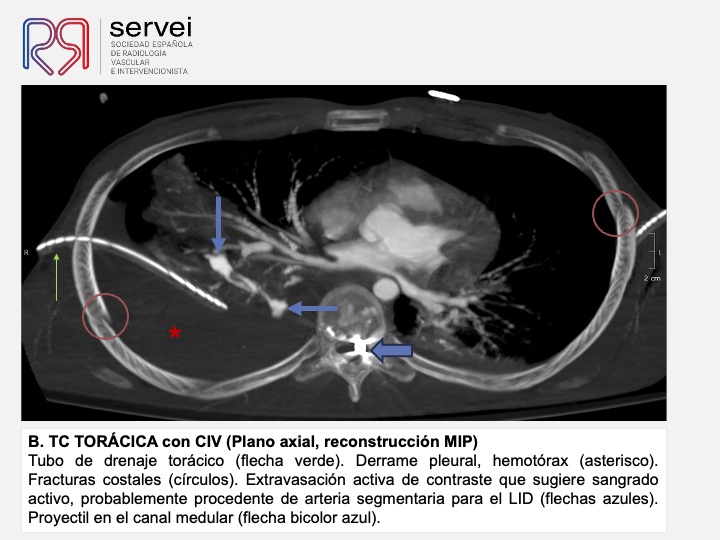

- Pseudoaneurisma pulnonar herida arma fuego 04